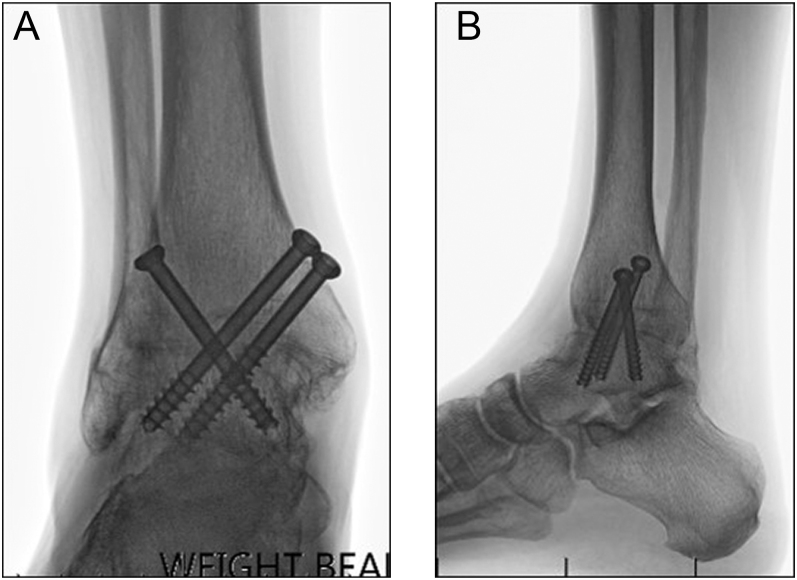

Arthroscopic ankle arthrodesis (AAA) has been performed for 40 years for end-stage ankle osteoarthritis. Along with open ankle arthrodesis (OAA) and total ankle replacement (TAR), it forms one arm of the triumvirate of commonly performed procedures for this condition. The aim of this article is to review the state of the art for AAA and compare outcomes with OAA and TAR. This narrative review of the literature traces the development of this technique through case series and systematic reviews. Traditional OAA techniques carry a nonunion rate of 11%, necessitating revision surgery in most cases. As individual and communal experience of AAA has grown, the range of pathology and deformity successfully corrected by this technique has developed. There is evidence that AAA offers greater and more rapid union rates, with reduced hospital stay and better long-term outcomes. However, the technique requires mature surgical skills and still carries a significant complication rate. No single procedure is suitable for all patients. AAA can be seen as the new gold standard for patients with isolated ankle osteoarthritis and no/minimal deformity, either within the talocrural joint or hindfoot or patients with systemic and/or local comorbidities that would benefit from minimal disturbance to the soft-tissue envelope. However, in older patients, the presence of concomitant hindfoot osteoarthritis or significant deformity, TAR and OAA remain valuable procedures in the foot and ankle surgeon's armamentarium.